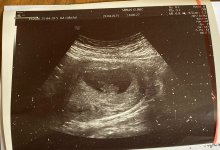

merhaba, bir ultrason görüntüm var 5haftalik Keseye göre cinsiyet tahminizi bekliyorum şimdiden teşekkürler 🥰

Resim ters şimdi farkettim

Hayırlı olsun canım genelde erkek bebek kesesi muz şeklinde olur kız bebek kesesi yuvarlak derler ama batıl inanç hurafe diyen de var ama oğlumda kesesi muz şeklindeydi şu an ikinciye hamileyim yuvarlak badem şeklinde ama daha Cinsiyeti belli değil Rabbim gönlüne göre versin